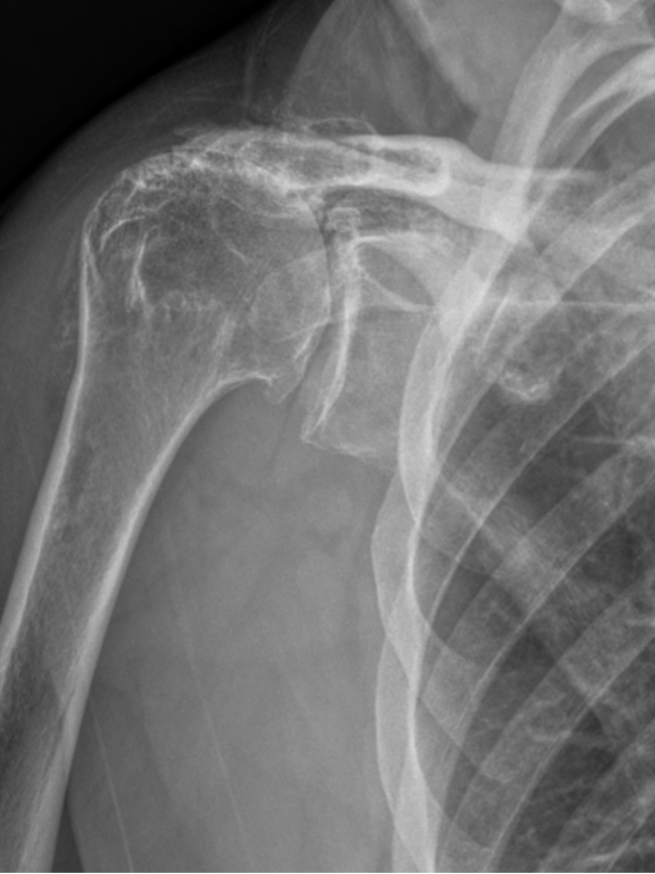

Proximal Humerus Fracture

Concentric Arthritis

Eccentric Arthritis